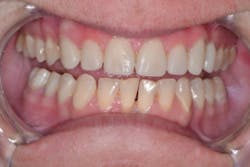

At the post-operative visit two weeks later, the contacts were perfect, and I achieved anterior disclusion in all excursions. No other refinement of the restorations was needed other than polishing of the surfaces, which required minimal effort. Activa has a chameleon effect that blends shades and reflects adjacent hues to create a natural esthetic.

Although four-year cases with Activa have been reported, only time will tell what the longevity of this case will be. So far, the case is at six months and counting confidently (figures 8 and 9). The durability of Activa has been reported in the literature. A patented, rubberized-resin molecule in the resin matrix absorbs shock and stress, and provides unique flexural strength that resists chipping and fracture. A far more expensive option that requires laboratory-fabricated porcelain crowns might provide a more esthetic result, but it was not a viable possibility in this case. The esthetic outcome achieved with this direct restorative technique is very good, and we know we did the right thing for this particular patient.